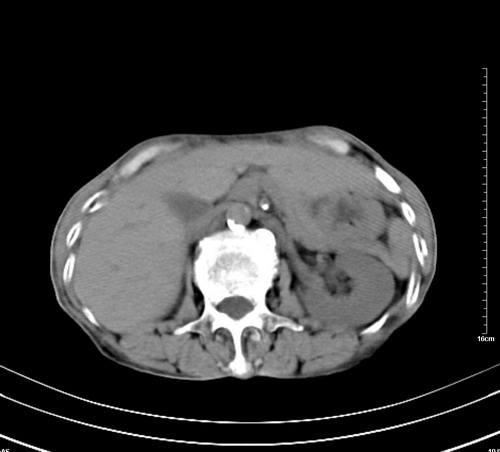

1 气管旁、隆突下淋巴结明显肿大,肝左叶外侧段低密影,都考虑转移。

2 肝右后叶下段明显增大,片状低密影,但因各种伪影显示不佳,不排除病变。

肺癌,纵隔淋巴结转移,肝左叶病变考虑为转移病灶。

后中纵隔团块影,伴气管、食道受压移位,首先考虑转移瘤,肝s5段低密度灶。建议增强检查,另外其结肠是否有问题请提供,右肺部分肺叶局限含气增多,考虑局限肺气肿。

后中纵隔团块影,伴气管、食道受压移位,首先考虑转移瘤,肝表现同11773。